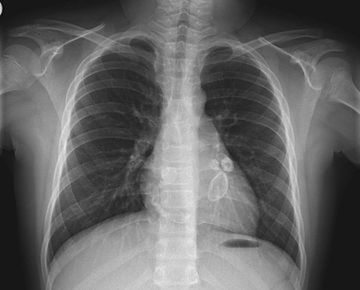

Tętniakowate zmiany i zwapnienia naczyń wieńcowych widoczne na przeglądowym radiogramie klatki piersiowej pacjenta z chorobą Kawasakiego

Tętniakowate zmiany i zwapnienia naczyń wieńcowych widoczne na przeglądowym radiogramie klatki piersiowej pacjenta z chorobą Kawasakiego © Wikipedia